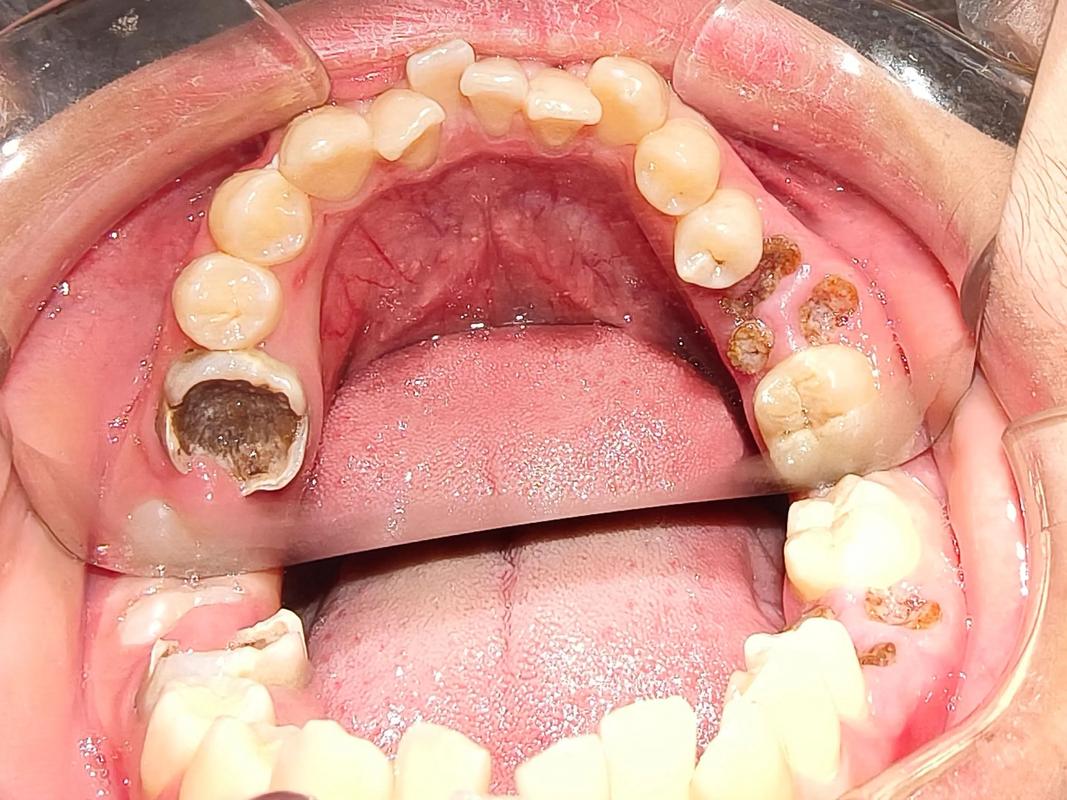

(图片来源网络,侵删)

最常见的类型:龋齿 (Cavities / Dental Caries)

这是我们通常所说的“蛀牙”,由细菌分解食物残渣产生酸,腐蚀牙齿造成的,根据严重程度,又可以细分为:

深龋

- 俗称:牙本质深层龋。

- 描述:蛀洞非常深,已经接近牙齿最核心的牙髓(神经),对冷热刺激的疼痛感非常强烈,并且是一过性、尖锐的剧痛,吃东西时容易塞食物,引起疼痛。

- 处理:情况比较复杂,如果牙髓还没有发炎,可以做垫底补牙;如果已经感染或发炎,就需要做根管治疗(抽神经),之后再进行牙冠修复。